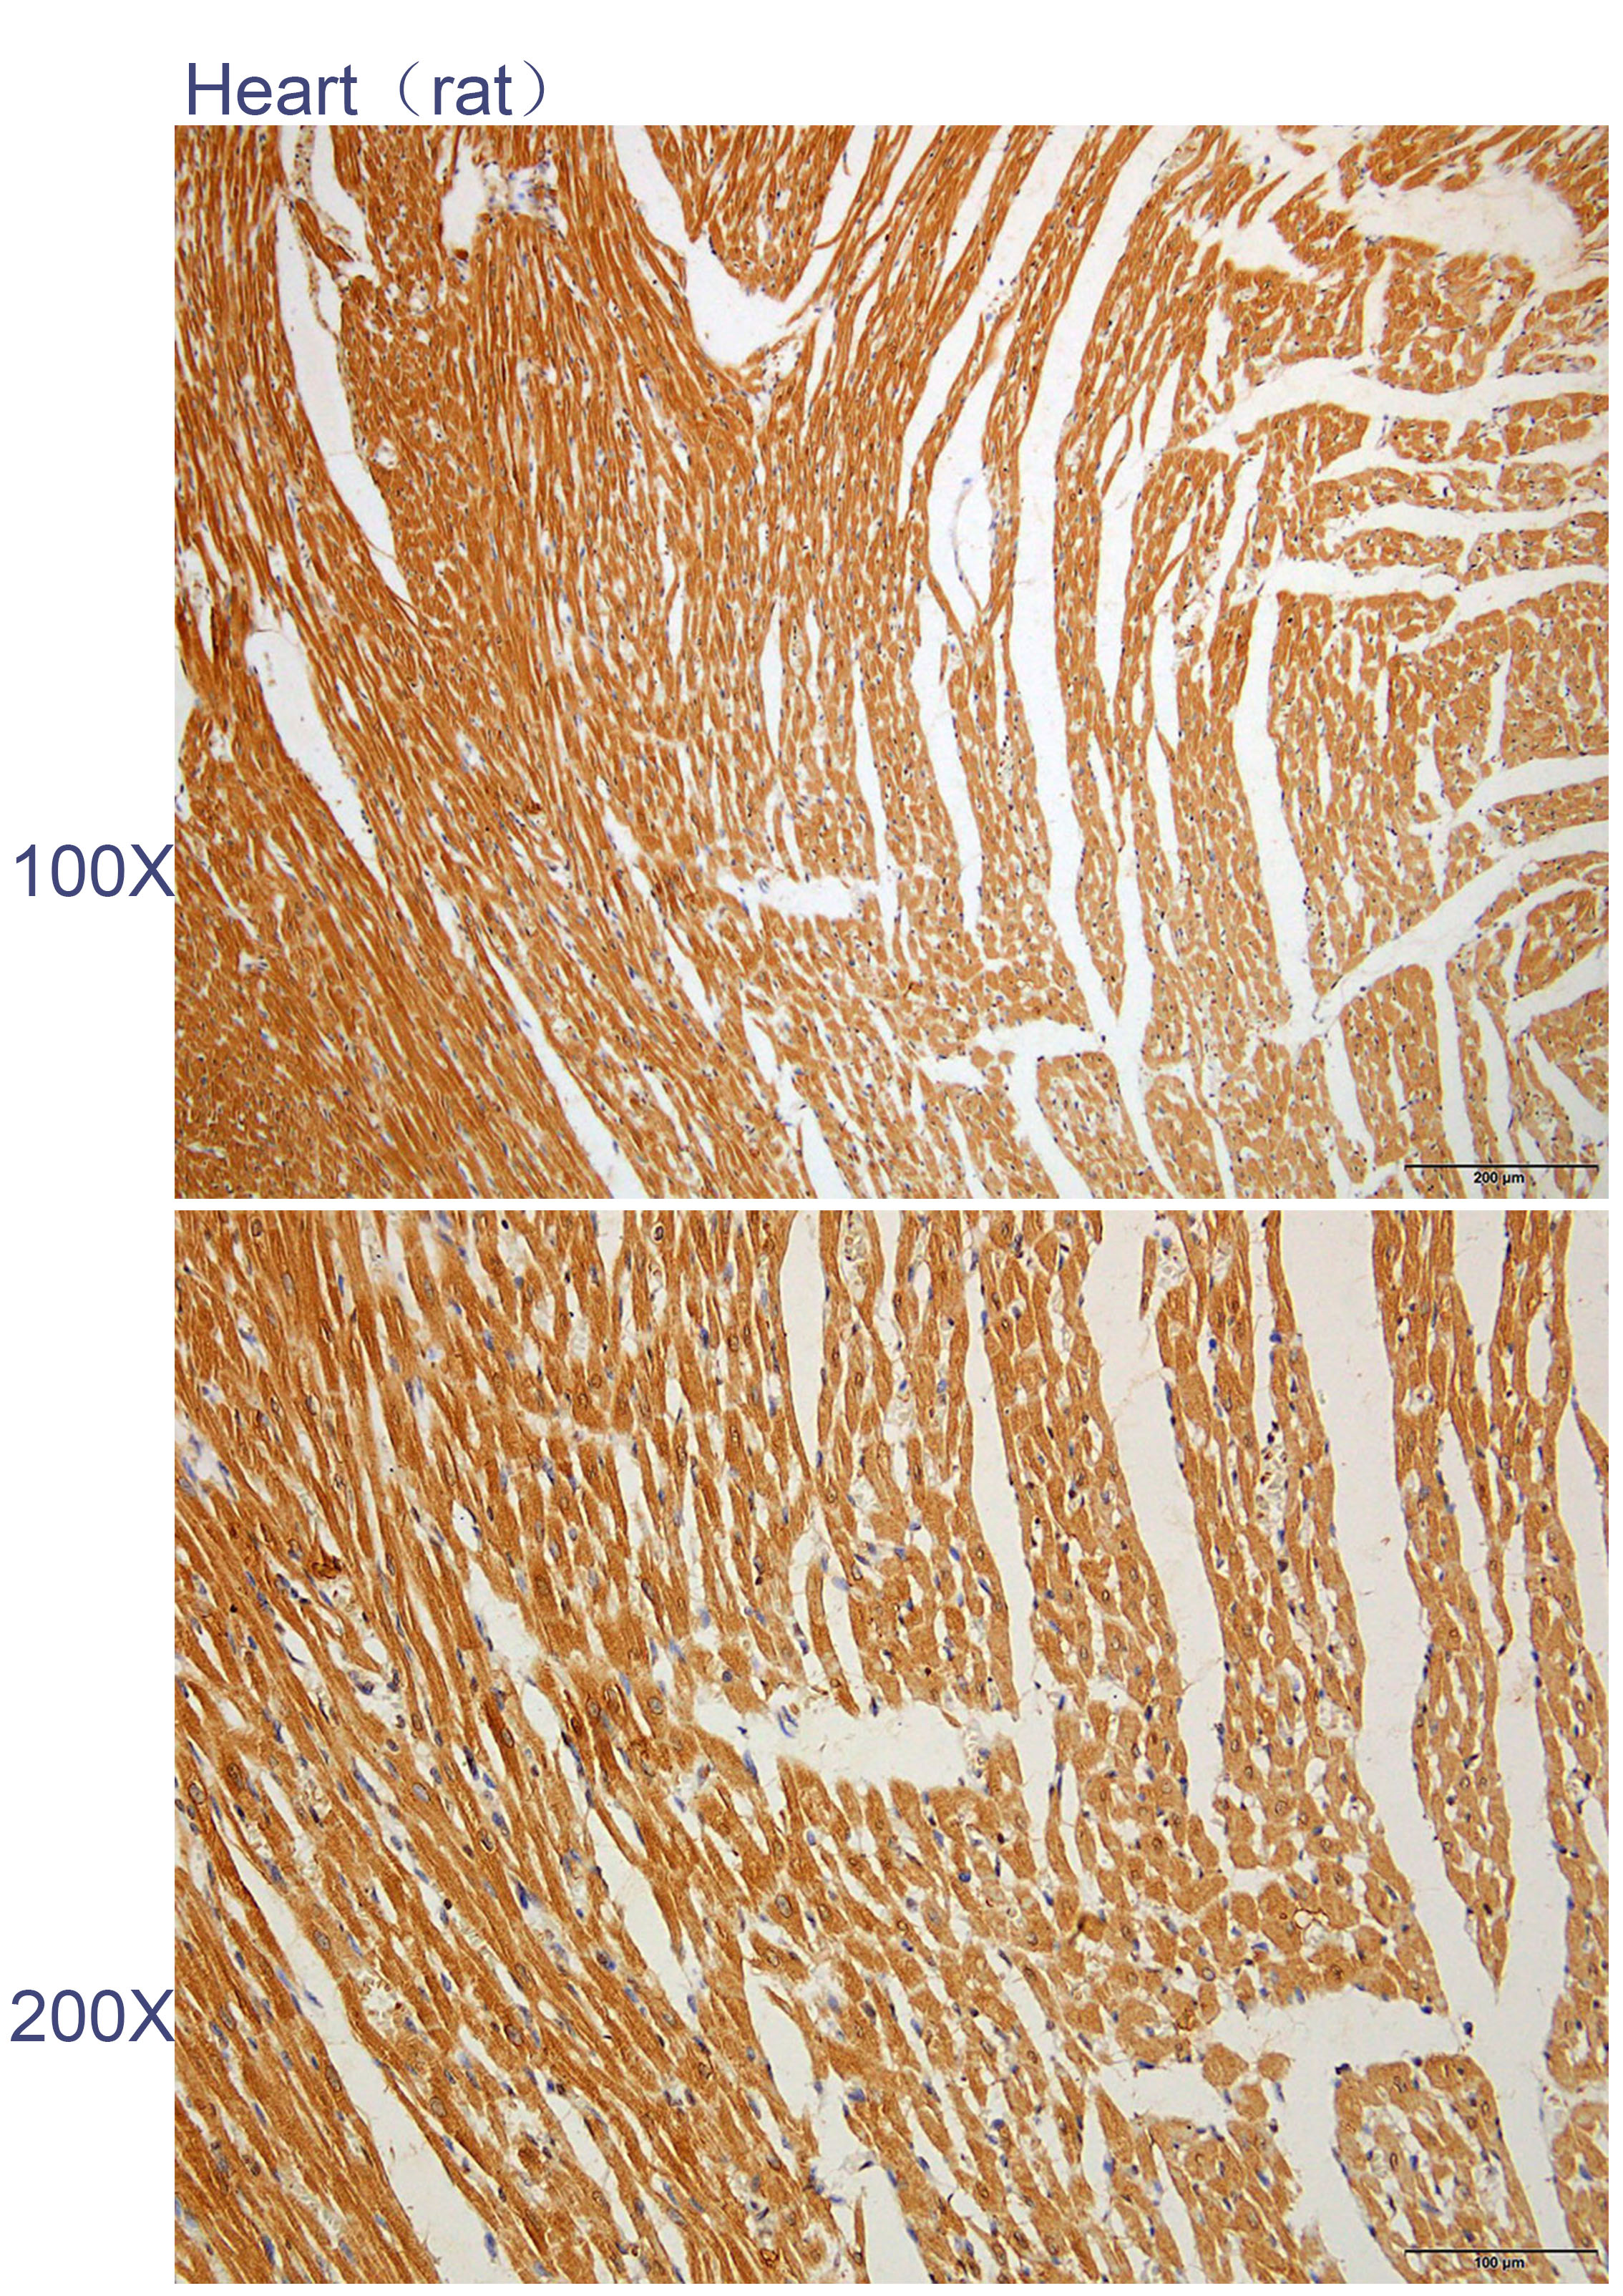

Immunohistochemistry of paraffin-embedded Rat heart with KMO antibody diluted at 1:100